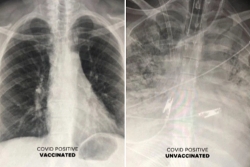

Phim chụp cho thấy tác động của virus SARS-CoV-2 đối với phổi của những bệnh nhân Covid-19 đã hoặc chưa chủng ngừa. |